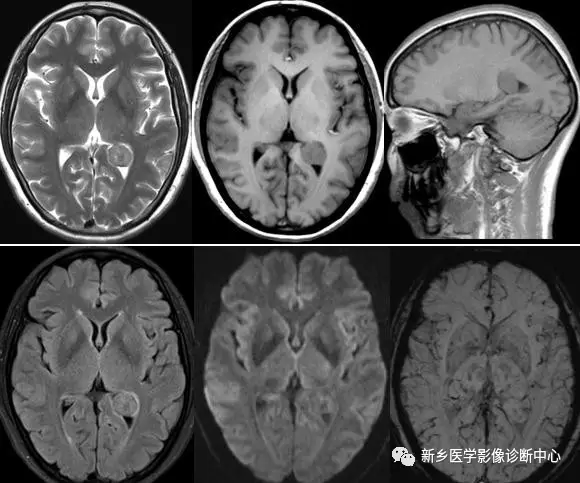

訊號:長T1長T2為主的不均質訊號,是由於瘤細胞的間變性,發育不成熟,細胞含水量大且形態不規則。

壞死:腫瘤的不均勻快速增長使得中心部位缺血、缺氧而壞死。

出血:供瘤血管多不成熟,功能不全,故出血後易導致區域性含鐵血黃素沉積。

侵襲性:突破中線累及對側腦組織,“蝴蝶徵”;沿室管膜播散。

共性:表現為明顯的不均質,T1WI呈等、低訊號,T2WI呈等、稍高訊號,瘤內可有出血、囊變、壞死,腫瘤實性部分DWI呈高訊號,ADC圖呈等、低訊號,增強呈明顯不均勻強化,典型的表現為花環樣、簇狀強化。

特性:腫瘤沿室管膜、室管膜下和白質纖維、周圍腦質播散明顯廣泛,可出現腦積水。